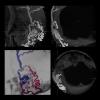

This is an example of a new endoscopic virtual peritoneal inflation tool on the patient's computed tomography (CT) imaging to aid in pre-procedural planning of endoscopic procedures. This is a new software feature on Fujifilm's Synapse 3D advanced visualization software released at the Healthcare Information Management and Systems Society (HIMSS) 2019 meeting. The software also enables 3-D imaging for surgical pre-procedural planning to assess the best entry points and angles.

This is an example of a 3-D printed pelvis that had multiple hip fractures and a second printed pelvis is from a post surgical repair CT scan, showing the pins and plates in pink. This was on display at the GE Healthcare booth at the Healthcare Information Management and Systems Society (HIMSS) 2019 conference. The files for printing were created from the CT datasets using the AW Advanced Visualization software.

This is an example of an arterial venous malformation (AVM) in the brain imaged on a Canon Alphenix Alpha angiography system. It shjows a contrast injection highlighting the vessels, which have been color coded to show the position of the veins and arteries involved in this vascular defect.